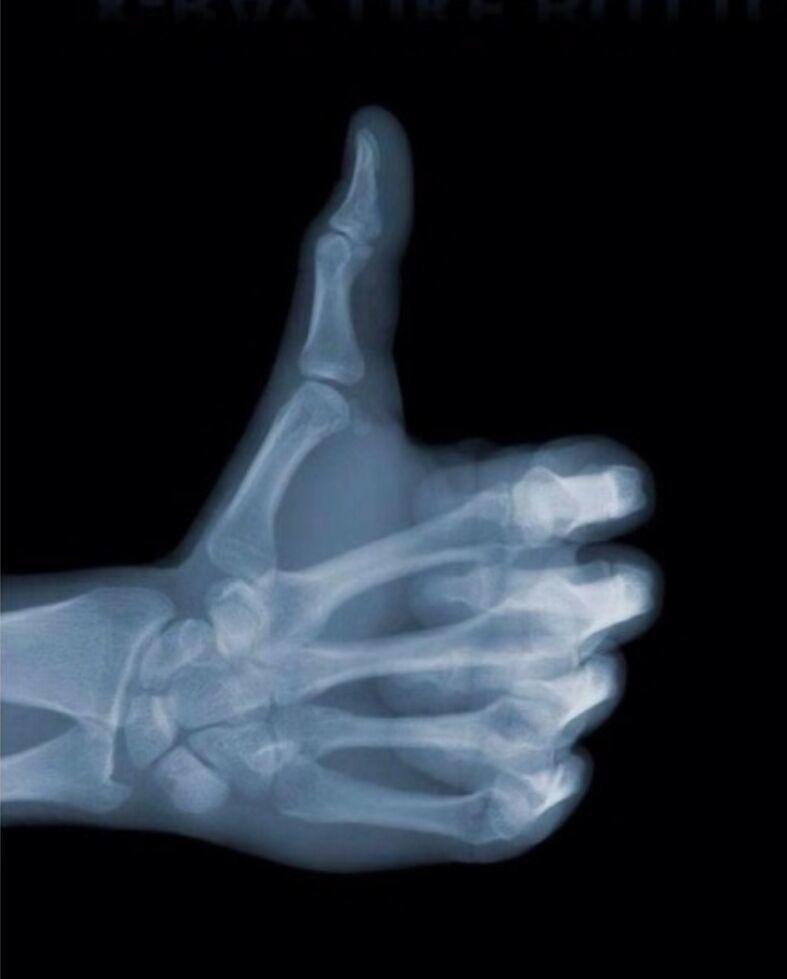

Readers generally have some understanding of X-rays in everyday life; they may know that white areas represent bones, while gray and black areas represent other tissues.

But this looks quite powerful. Different tissues and areas present different colors, which is directly related to tissue density. The higher the tissue density, the more X-rays are absorbed, resulting in a brighter image. Therefore, in X-ray imaging, the white areas are referred to as high density, while gray and black areas are referred to as low density. If a lesion causes a change in tissue density, after reaching a certain extent, changes in black, white, and gray levels will appear in the imaging.